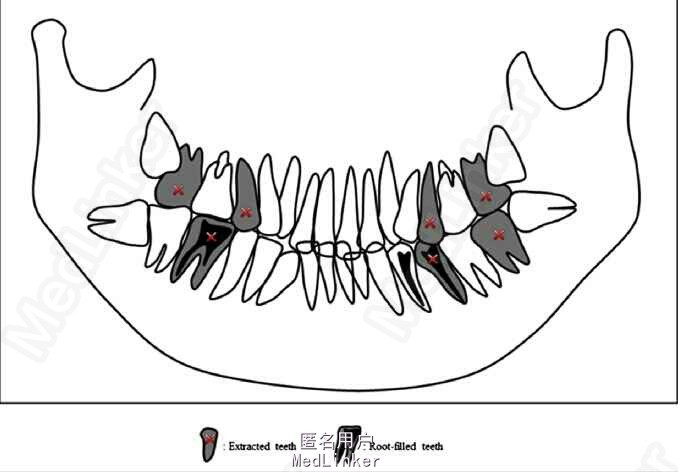

诊断:安氏II类1分类,双颌前突,牙列严重拥挤,左下7锁合,双侧上7牙根吸收,四颗第三磨牙阻生 治疗目标:减少唇的突度及前牙拥挤,扶正4颗阻生的第三磨牙,达到良好的面部美观和功能咬合。 治疗:上颌拔除2颗5和2颗7(不拔4的原因为左上4为正常牙,左上5大面积充填;右上4形态较右上5好。因拔除了坏牙保留了健康牙齿,但是拔5不利于前牙的内收,所以于上后牙56之间植入了支抗钉加强支抗,辅助内收前牙。拔7原因为两颗7远中面均有牙根吸收且有大面积充填),下颌左侧拔除5和7(左下5根管治疗且根尖阴影,拔除左下7原因为严重锁合,改正困难且容易导致上下磨牙的伸长加重II类高角面型),右侧拔除根管治疗且大面积充填后的6;分别竖直4颗近中倾斜阻生的8,整个疗程39个月,四颗8成功的代替6或7。双侧I类尖牙关系,左侧磨牙I类关系,右侧磨牙完全远中关系。唇突度改善,全景片可见达到可接受的牙根平行度,4个8完全萌出直立。以前因为锁合导致的两侧咬合不对称没有了。